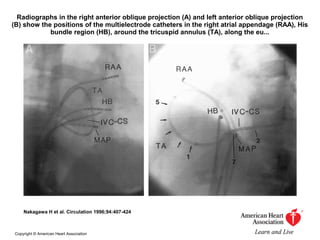

Radiographs in the right anterior oblique projection (A) and left anterior oblique projection

(B) show the positions of the multielectrode catheters in the right atrial appendage (RAA), His

bundle region (HB), around the tricuspid annulus (TA), along the eu...

Nakagawa H et al. Circulation 1996;94:407-424

Copyright © American Heart Association